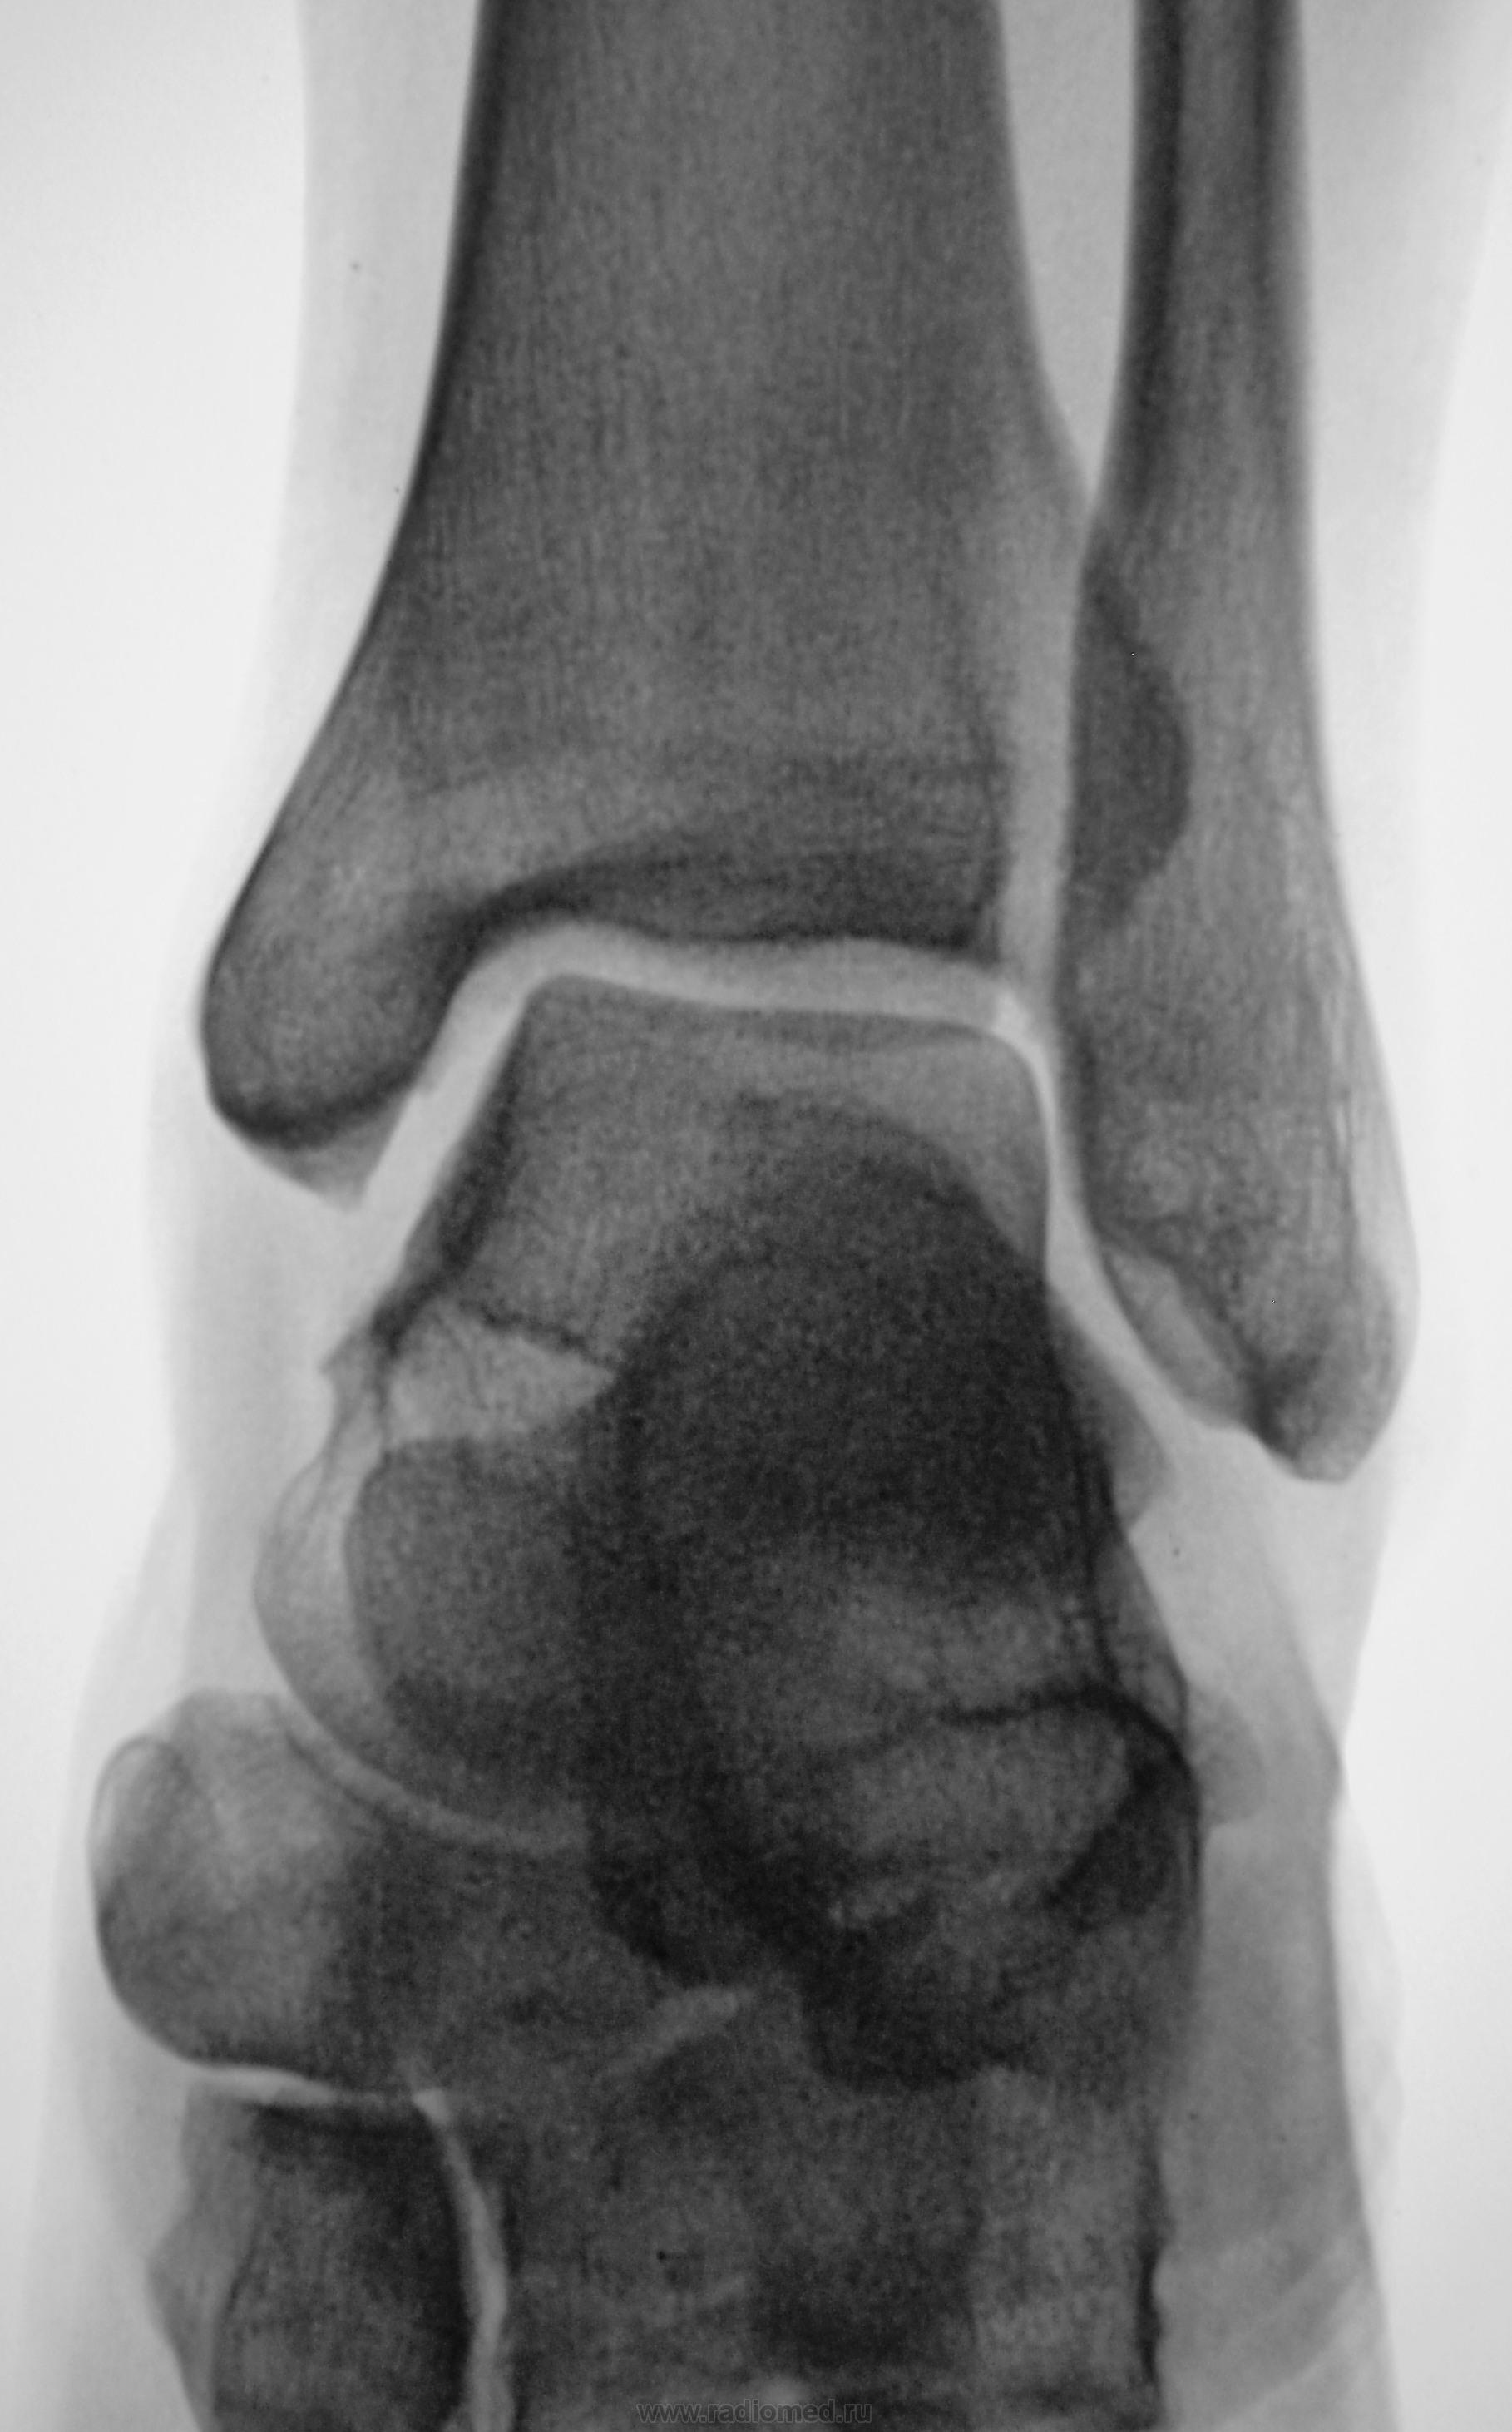

Травма.  Пациент направлен на рентгенографию голеностопного сустава.

Валентин Львович, Вы опять что-то каверзное припасли? Нужно сделать томографию - глядишь, все кости будут переломаны. Особливо прискіпливо(укр.) посмотреть на т.н. переднюю лодыжку.

Так и чем завершилось, Валентин Львович? Без костно-травматических?

Я не знаю, не знаю до сих пор.